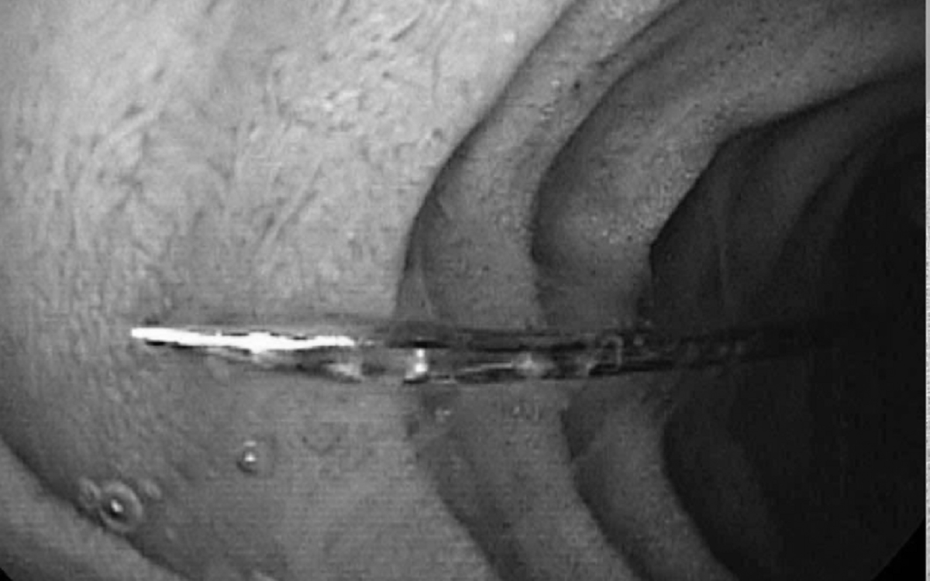

Chiếc kim may được lấy ra. Ảnh BVCC.

BS.CKII Lê Đức Lộc – khoa Tiêu hoá cùng ê-kíp phẫu thuật đã nhanh chóng tiến hành thủ thuật nội soi thực quản, dạ dày và gắp dị vật.

Khi đưa ống soi mềm qua đường miệng vào ống tiêu hóa trên, ghi nhận dị vật kim may nằm ở vị trí D2 tá tràng, kèm xước nhẹ niêm mạc hành tá tràng. Dị vật sau đó đã được các bác sĩ gắp ra an toàn. Hiện sức khỏe bé đã ổn định và đang hồi phục tốt.